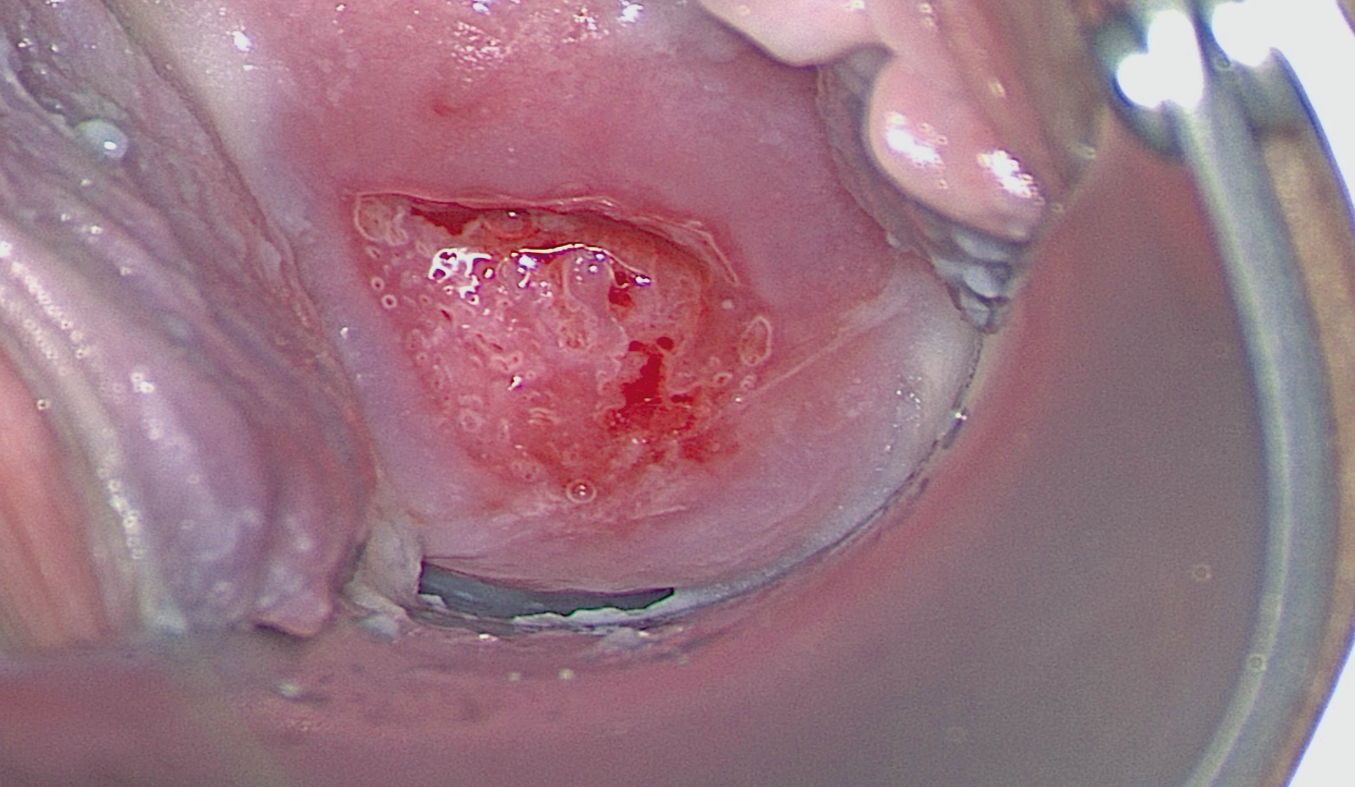

Atypical transformation zone type 1, minor change.